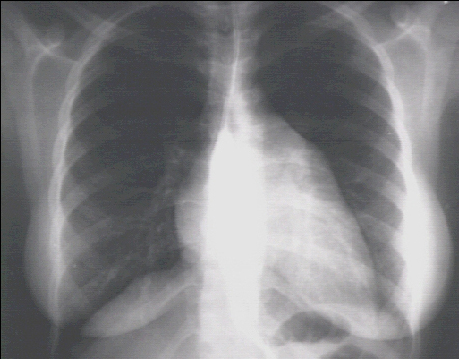

PA view

These chest X rays show left ventricular enlargement and left atrial enlargement. This PA view demonstrates the enlarged left ventricle as an increase in the inferolateral cardiac border associated with an increased cardiothoracic ratio .

The markedly enlarged left atrium is manifested by the double contour within the heart border, an elevated left mainstem bronchus, and an enlarged left atrial appendage. The lateral view with barium swallow, demonstrates posterior displacement of the esophagus by the markedly enlarged left atrium.